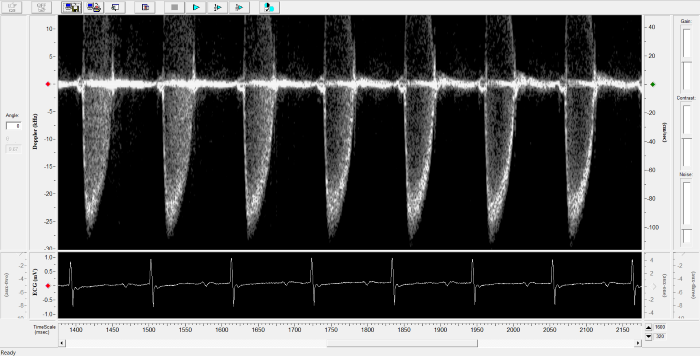

Renal Flow

Renal Flow. Image Credit: Scintica Instrumentation Inc.